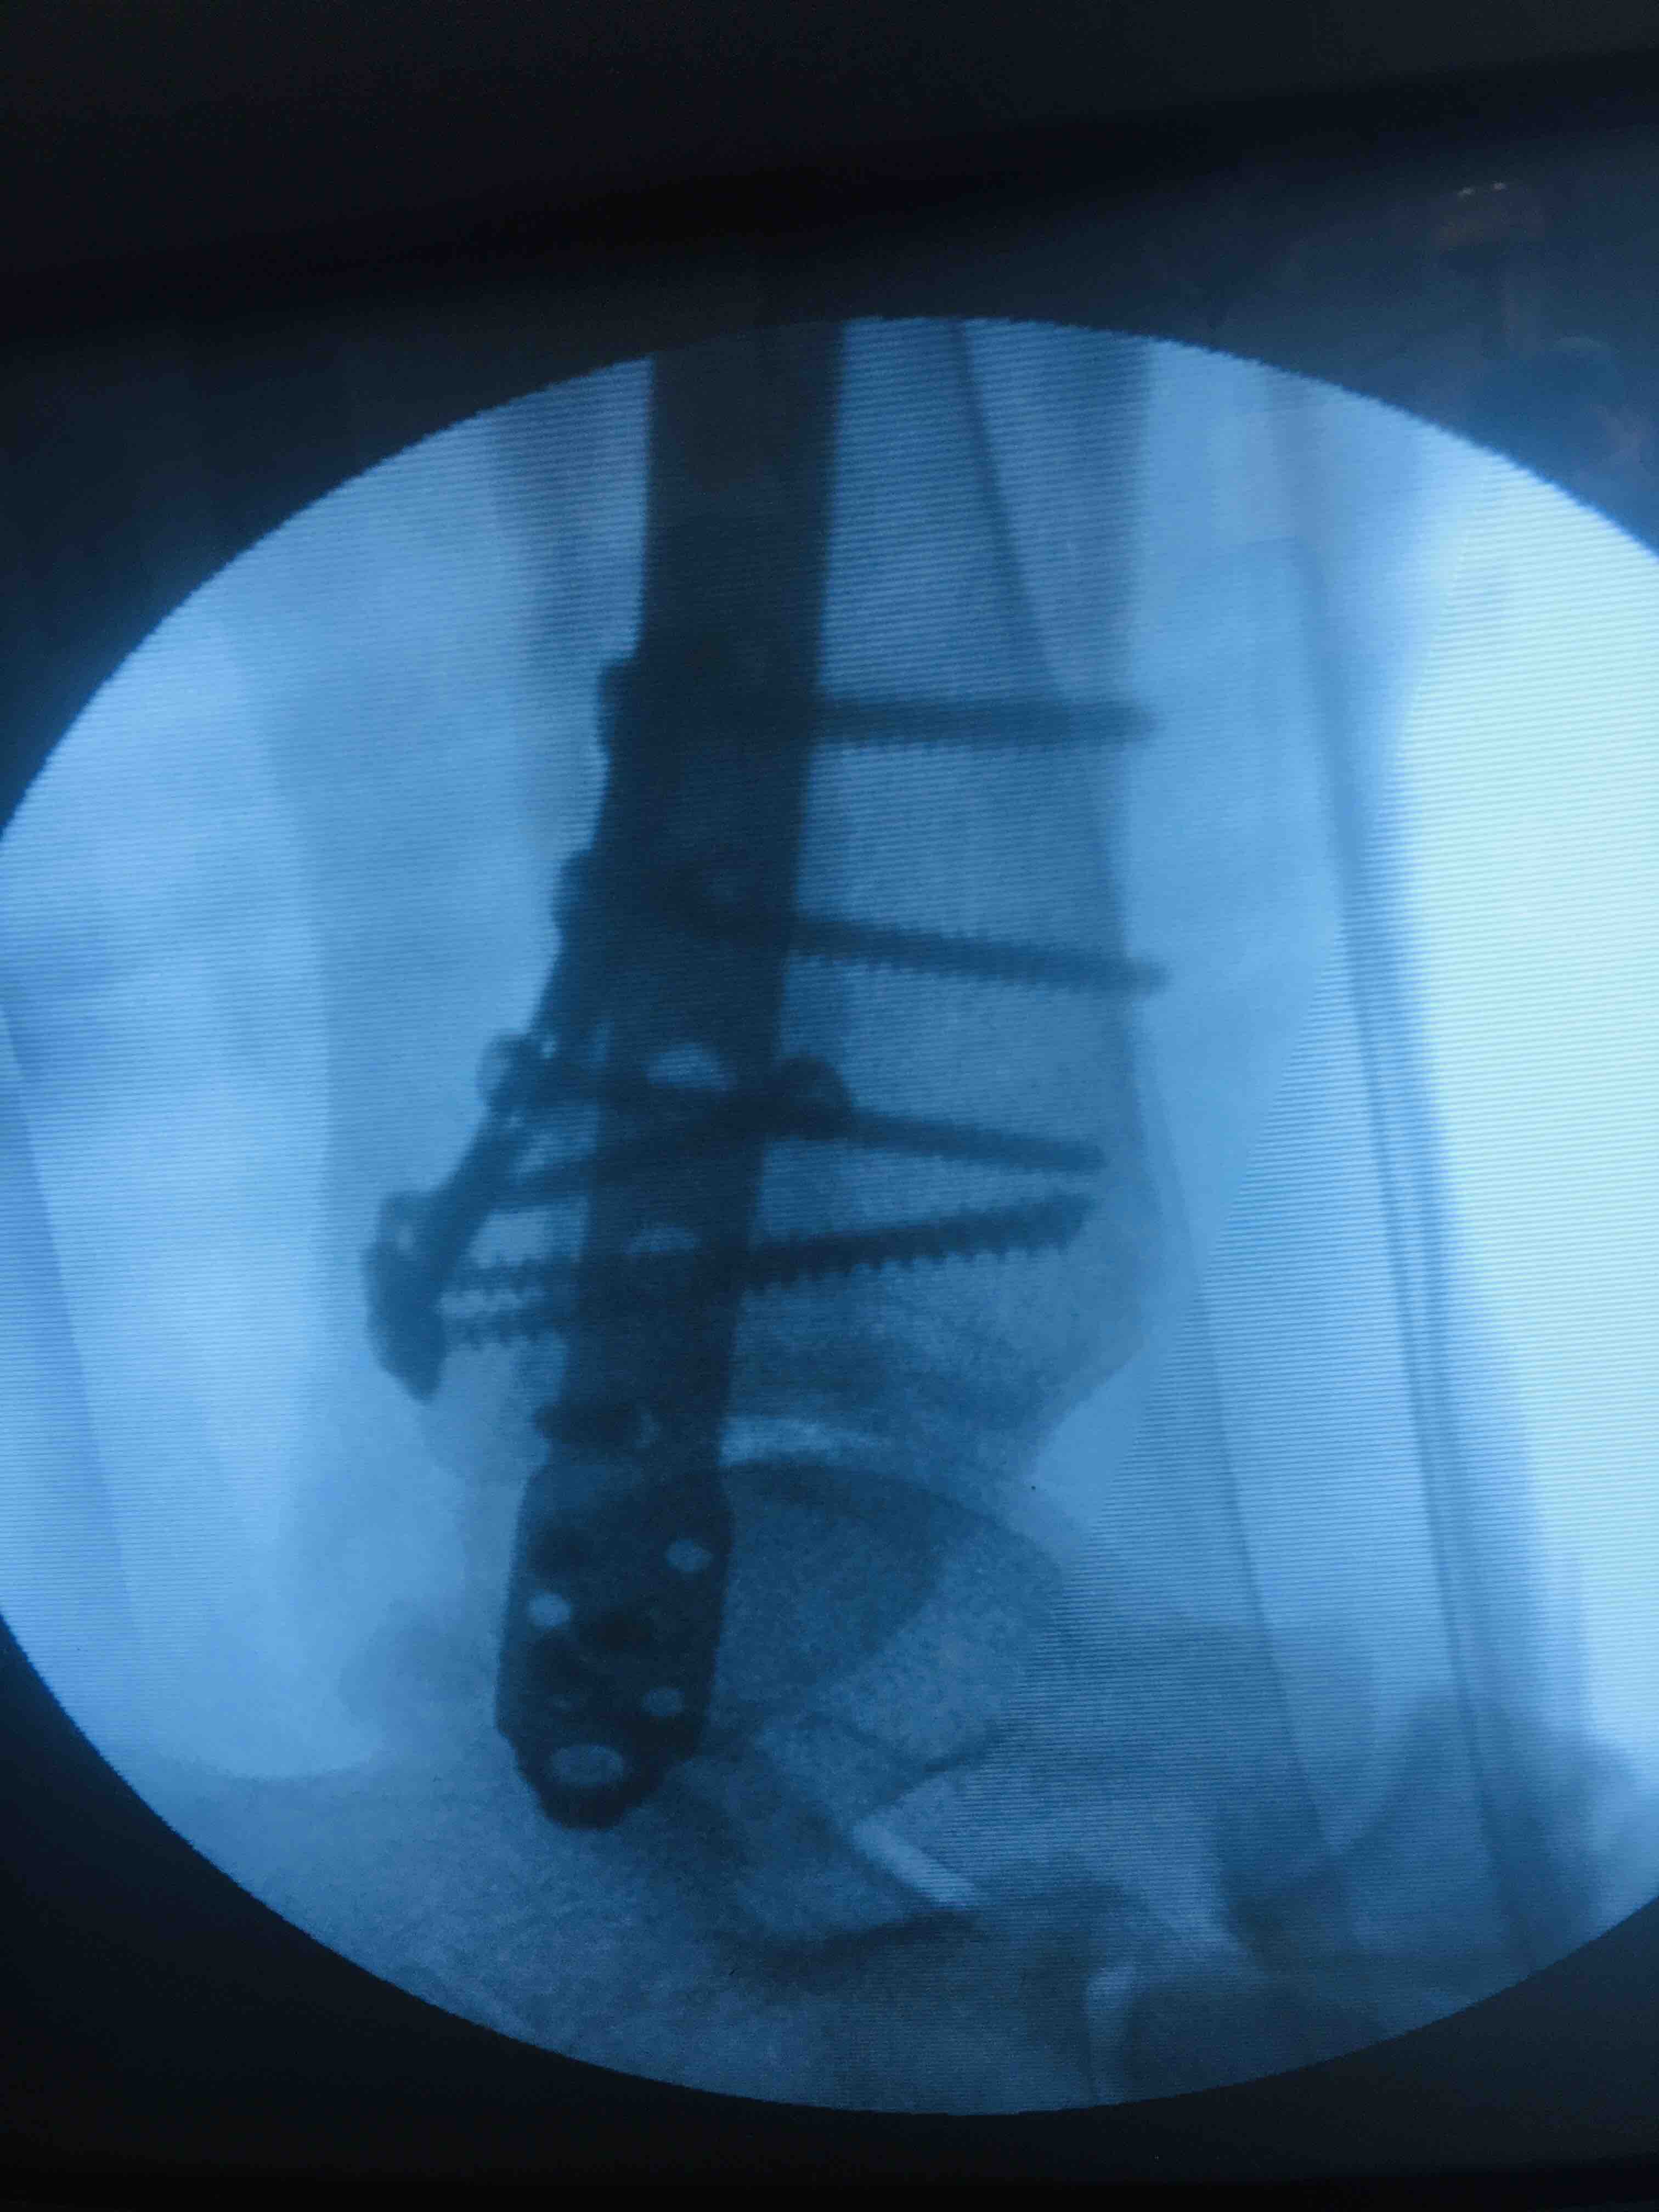

三踝骨折(切复内固定术)

骨折 踝骨折 三踝骨折

急诊行牵引术,待肿胀消除后行切复内固定术,术后抗炎消肿等处理。